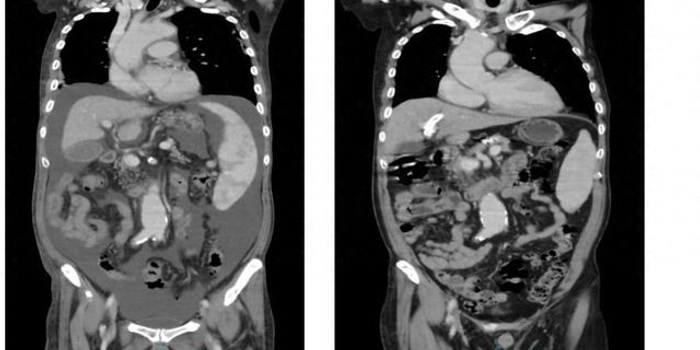

近日,青岛市中心医院放射介入科成功为一名肝硬化大出血患者完成“经颈静脉肝内门体静脉分流术”(TIPS)。该手术相当于人体内“都江堰工程”,难度大,被誉为综合介入手术中“皇冠上的明珠”。

患者韩先生(化名)患有酒精性肝硬化、贫血病史15年,长时间的酒精性肝脏硬化引起门静脉入肝阻力增大,表现为门静脉高压,门静脉压力只能通过食管胃底静脉等侧支循环逆向传导,久而久之食管胃底静脉压力会日渐增大,最后造成食管胃底静脉曲张破裂出血。韩先生既往就因反复呕血、黑便,成为医院的“常客”,曾于外院多次行内镜下套扎、硬化治疗。

然而,对韩先生来说,内镜下止血治标不治本。一周前,他再次出现大量呕血、便血、乏力及头晕,被家人紧急送往青岛市中心医院就诊。经内科治疗后出血暂时停止,由于韩先生胃底严重曲张的静脉血管发生过多次破裂出血,在体内犹如一颗定时炸弹,随时可能再次爆炸而引发大出血,甚至导致死亡。为彻底排除这个“隐患”,预防再次出血,经会诊,韩先生转入放射介入科,科室主任李雷建议他进行“经颈静脉肝内门体静脉分流术”治疗。

李雷主任向韩先生及家属详细解释了手术的原理,经颈静脉肝内门体静脉分流术是在X射线引导下经颈内静脉穿刺,通过在肝静脉/下腔静脉与门静脉之间的肝实质内建立人工分流通道(支架),使门静脉部分血流直接分流至心脏,以降低门静脉压力,从根本上解决患者发生消化道出血的源头,是治疗门静脉高压、食管胃静脉曲张出血、顽固性腹水的介入治疗技术。“河水泛滥只采取‘围堵’而不‘疏通’,压力大时别的地方还会泛滥,而经颈静脉肝内门体静脉分流微创手术相当于给河道疏通减压,预防再次出血,让身体内的这颗炸弹成为哑弹。”李雷主任比喻。

听了李主任的解释,韩先生和家属决定接受治疗,手术如期进行。术中,李雷主任1次穿刺便成功,为患者建立了人工分流通道,降低了门脉压力,并使用特殊材料栓塞导致出血的曲张静脉,术后患者自觉腹胀等不适症状亦明显好转。